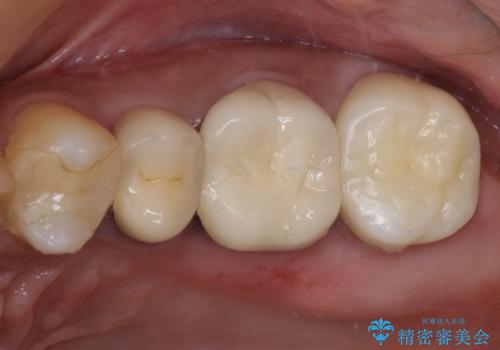

折角なのできれいに仕上げたいとのことで、オーダーメイドタイプのクラウンを選択されました。色調を周りのご自身の歯と合わせることができるため、自然な仕上がりをご希望の方におすすめです。